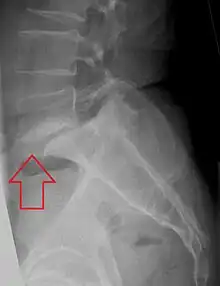

Grade 1 retrolistheses of C3 on C4 and C4 on C5

A retrolisthesis is a posterior displacement of one vertebral body with respect to the subjacent vertebra to a degree less than a luxation (dislocation). Retrolistheses are most easily diagnosed on lateral x-ray views of the spine. Views, where care has been taken to expose for a true lateral view without any rotation, offer the best diagnostic quality.

Retrolistheses are found most prominently in the cervical and lumbar region, but can also be seen in the thoracic area.